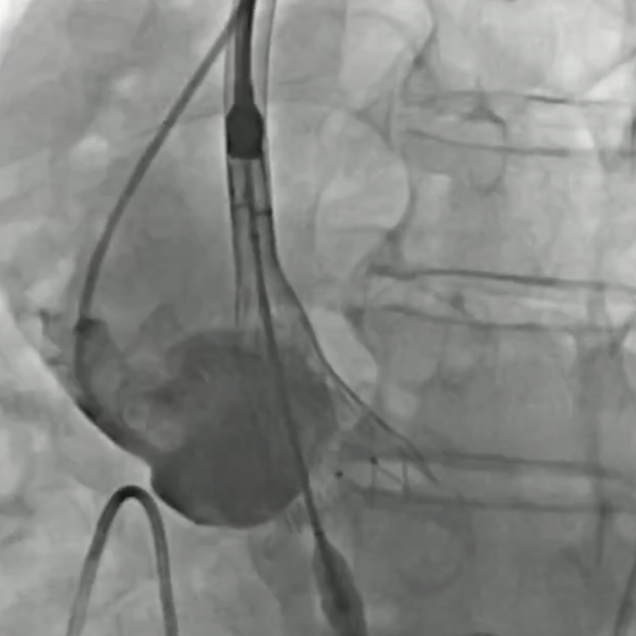

建立股静脉-房间隔-左房-左室-主动脉轨道

行二尖瓣球囊扩张

成功植入TAVR瓣膜